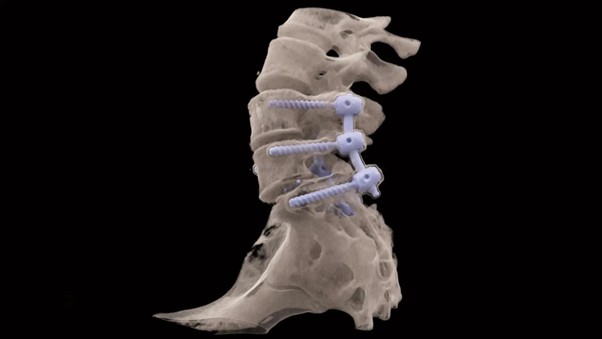

Снимок пояснично-крестцового отдела на Siemens SOMATOM X.Ceed без артефактов от металла.